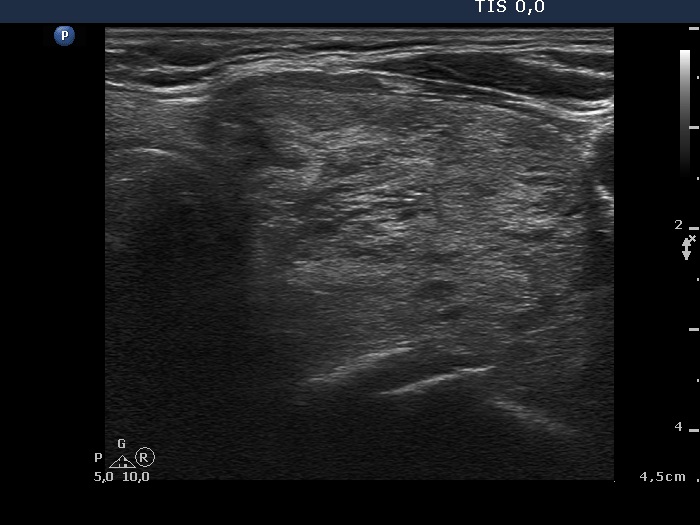

Ultrasonography. The thyroid was echonormal. There were several insignificant lesions in the right lobe. The left lobe presented a large nodule composed of discrete hyperechogenic areas. The lower pole of the lobe was clearly visible during swallowing (see video).